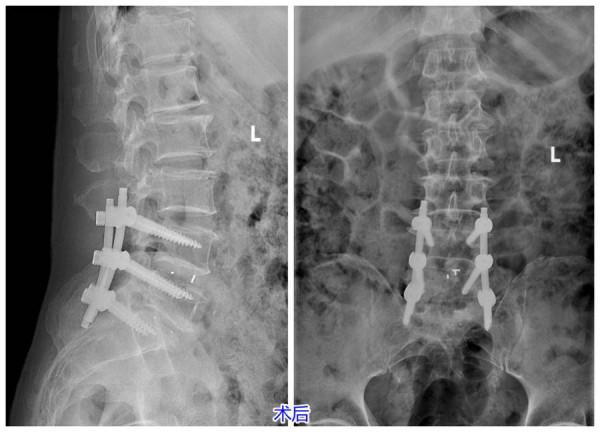

近期王先生慕名來到濟南南郊醫院,經骨二科副主任醫師管玉傑仔細詢問病史和相關檢查,診斷為腰椎管狹窄症(L4/5、L5/S1);腰1、2椎體血管瘤。“患者病史長、症狀重、嚴重影響日常生活,為避免神經進一步損傷,維持脊柱穩定性,需儘早進行手術治療。”骨二科醫師團隊進行病案討論後,最終為王先生制定了腰4/5、腰5/骶1椎管減壓+椎間盤切除術+椎間植骨融合釘棒內固定術的微創手術方案。

管玉傑副主任醫師表示:椎管狹窄症狀引發脊髓的神經損傷症狀,嚴重時甚至會導致下肢不全癱。當椎管狹窄,進行保守治療不能糾正時一定要儘早考慮手術治療。該手術方案是目前治療腰椎管狹窄症的常用微創手術,可最大程度地保留了人體的正常組織,達到神經組織的有效減壓,為神經功能的快速恢復創造了條件。它具有安全有效、創傷小、術中出血少、術後早期下地、恢復快、減少了術後切口感染以及臥床時間過長帶來的一系列併發症。

經過精心的術前準備後,骨二科副主任醫師管玉傑、副主任王光明、主治醫生劉通順利為患者完成手術。從根本上解決椎管狹窄情況,解除神經根壓迫情況,避免神經損傷進一步加重。術後第二天患者表示終於可以睡一個好覺、腰不疼了、渾身都覺得輕鬆了。